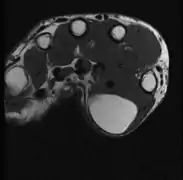

MRI showing lipoma of the arm

A physical exam is typically the easiest way to diagnose it. Rarely, a tissue biopsy or imaging may be required. The imaging modality of choice is magnetic resonance imaging (MRI) because it has superior sensitivity of distinguishing it from liposarcoma as well as mapping the surrounding anatomy.[22]